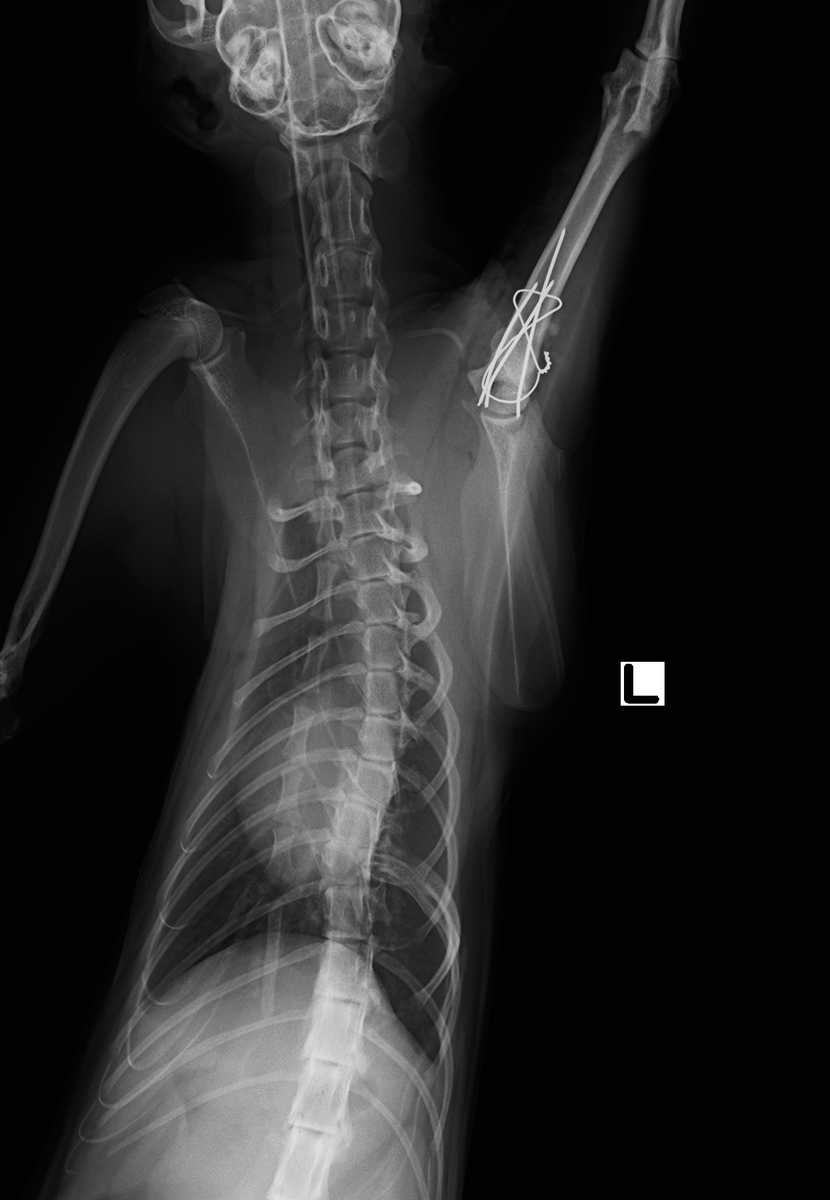

今回はピンとワイヤーを用いて整復手術を行いました。

術後直後のレントゲン写真です。